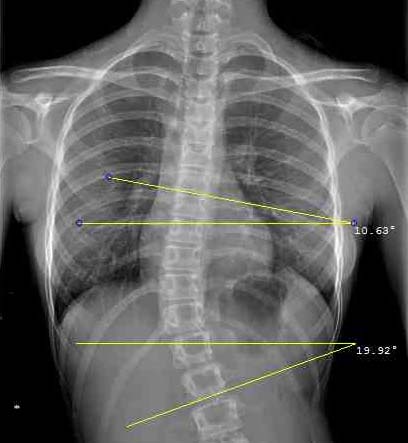

L'ANGOLO DI COBB

L’angolo di Cobb è l’angolo compreso tra le tangenti superiore e inferiore delle vertebre limite della curva (le più inclinate). L’inclinometro è molto utile per individuare rapidamente sulla radiografia le vertebre più inclinate.

Sulla radiografia tradizionale l’angolo può essere costruito con matita e righello e misurato con un goniometro. Più semplicemente può essere calcolato con l’inclinometro accostando lo strumento al bordo delle vertebre limite, superiore e inferiore, e sommando l’inclinazione delle due vertebre.

Sul PC l’angolo di Cobb viene pure calcolato sommando l’inclinazione delle vertebre limite rispetto l’orizzontale, utilizzando gli strumenti presenti nel dischetto.

Quando il bordo vertebrale non è identificabile con precisione può essere utilizzata come riferimento la linea tangente ai due peduncoli.